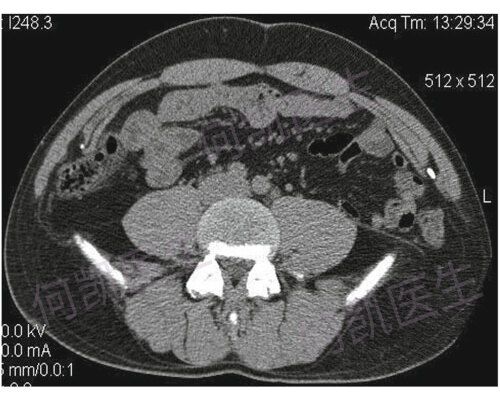

我院疝外科团队完成粤西首例完全腔镜下急诊嵌顿性腰疝tapp修补术